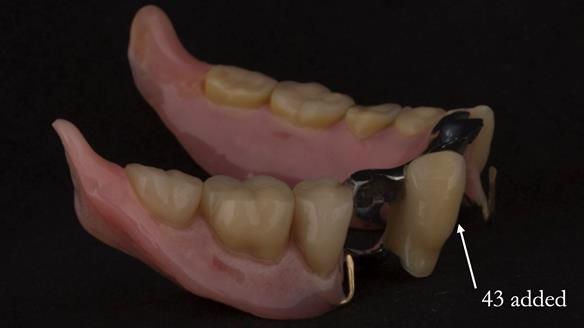

In 2022, tooth 43 fractured.

An artificial tooth was added to the RPD

by welding a cobalt–chrome tag to the bar

and adding the tooth.

The denture continued to function extremely well.